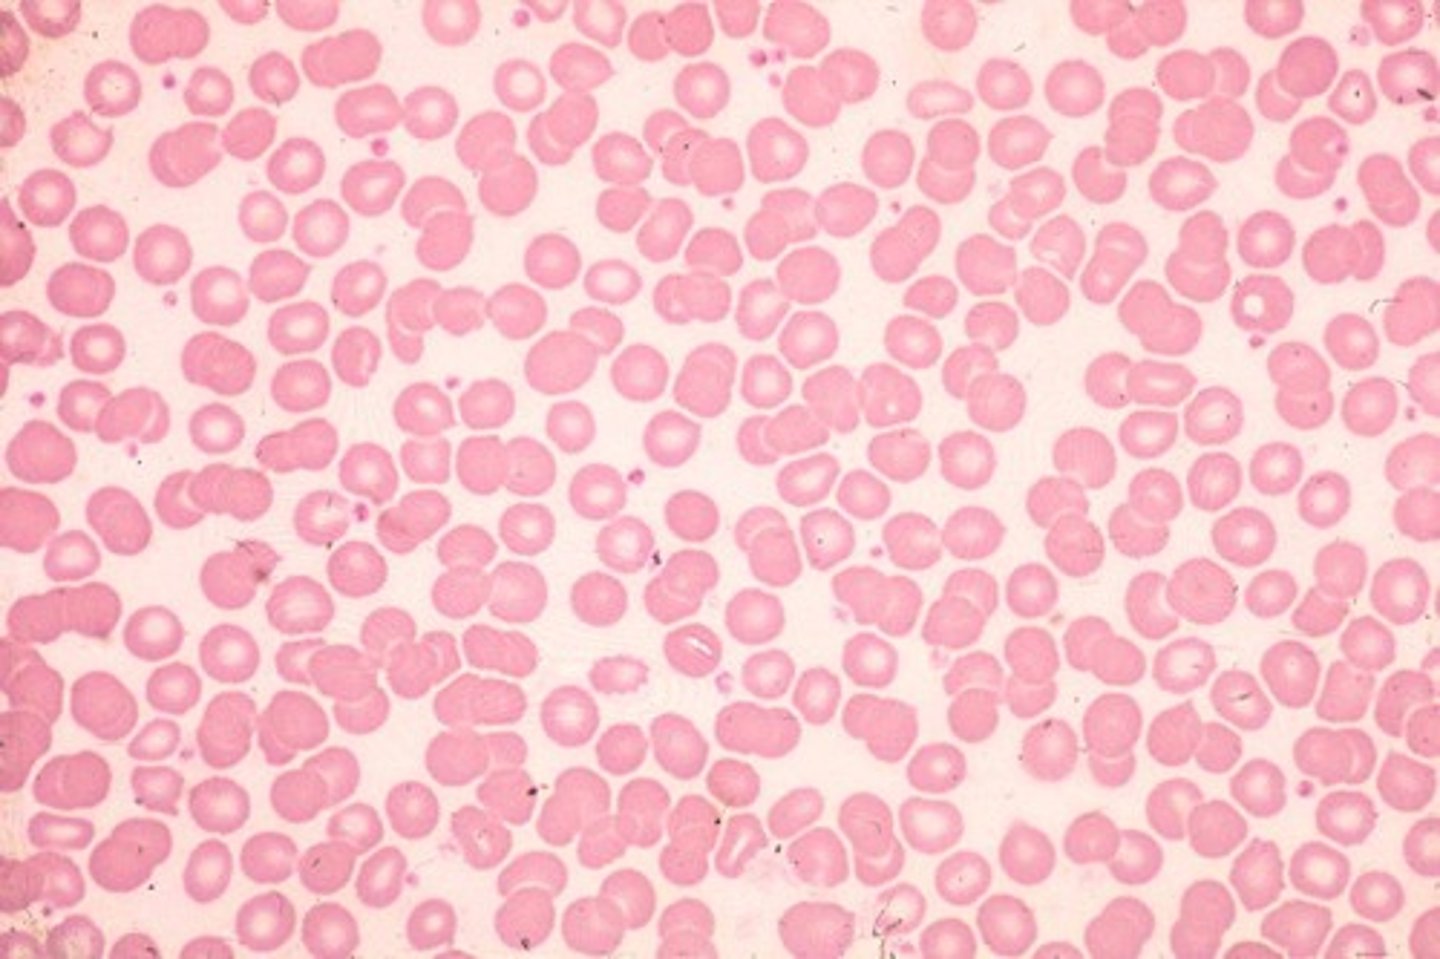

Blood

What is this?

Red Blood Cell

what is this?